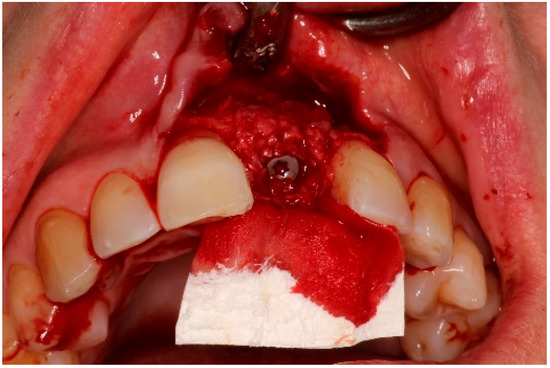

4. Timeline and Diagnostic Assessment

5. Therapeutic Intervention

5.2. Non-Surgical Pre-Treatment

5.3. Surgical Treatment